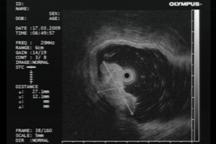

По данным ЭУЗИ, эндосонограммы пациентов со всеми формами лимфом демонстрируют их отличительный признак - в области визуально измененной слизистой оболочки при сканировании стенка желудка утолщена за счет гиперэхогенного неоднородного подслизистого и глубоких слоев слизистого слоя, а между патологическими зонами визуализируются участки нормальной пятислойной стенки желудка (рис.4).

Рис. 4. 58 лет. Язвенно-инфильтративная лимфома. Заключение иммуногистохимии: диффузная В-крупноклеточная лимфома желудка:

а - визуальная картина, требующая дифференциальной диагностики между язвенно-инфильтративным раком и язвенно-инфильтративной лимфомой тела желудка; б - эндосонограмма язвенно-инфильтративной лимфомы желудка, утолщенный гиперэхогенный подслизистый слой достигает 2,9 мм.